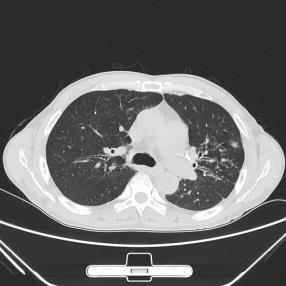

This paper proposes applying a novel deep-learning model, TBDLNet, to recognize CT images to classify multidrug-resistant and drug-sensitive tuberculosis automatically. The pre-trained ResNet50 is selected to extract features. Three randomized neural networks are used to alleviate the overfitting problem. The ensemble of three RNNs is applied to boost the robustness via majority voting. The proposed model is evaluated by five-fold cross-validation. Five indexes are selected in this paper, which are accuracy, sensitivity, precision, F1-score, and specificity. The TBDLNet achieves 0.9822 accuracy, 0.9815 specificity, 0.9823 precision, 0.9829 sensitivity, and 0.9826 F1-score, respectively. The TBDLNet is suitable for classifying multidrug-resistant tuberculosis and drug-sensitive tuberculosis. It can detect multidrug-resistant pulmonary tuberculosis as early as possible, which helps to adjust the treatment plan in time and improve the treatment effect.